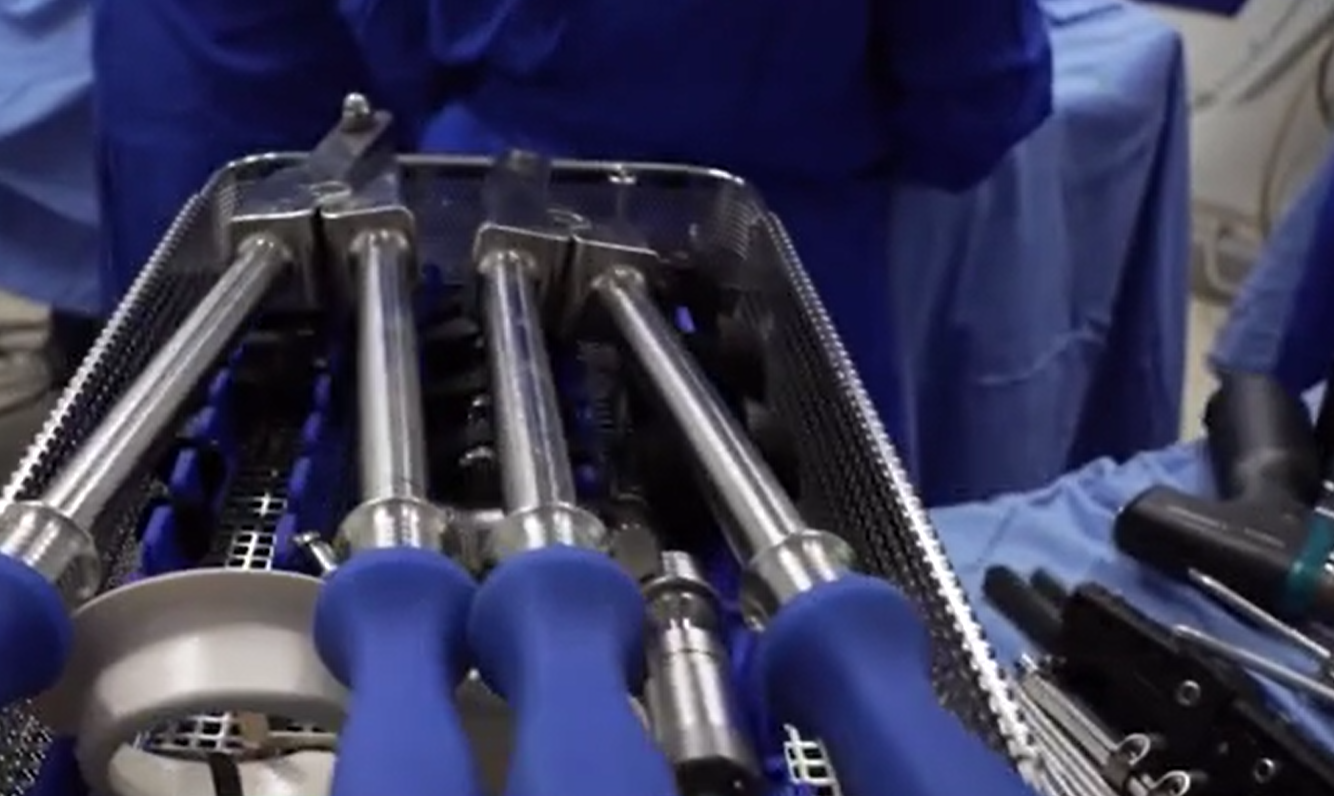

29歲男網紅科西奧(Yeferson Cossio)本身已有5呎8吋高,他說因有不方便說明的腳患問題,而決定在首都波哥大(Bogota)一診所做斷骨增高手術。手術涉及把其腿骨斷開,再加上金屬磁力支架,之後再用遙控方式將支架逐少伸長,拉長腿骨及肌肉組織。目前Cossio已接受手術4個月,據報每天可以增高約1毫米,若一切順利,他最終可以增高4吋。